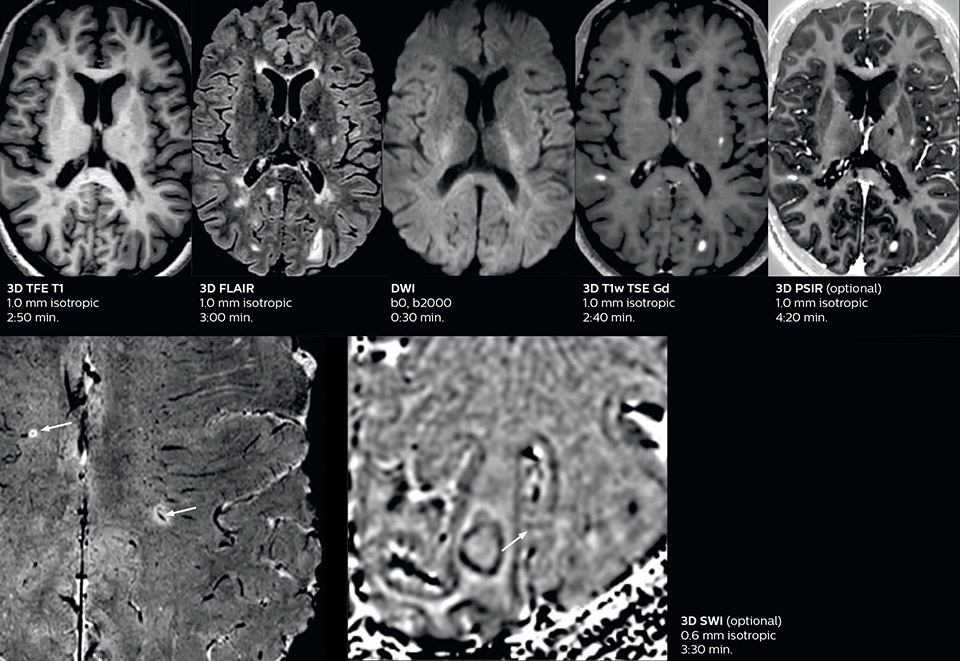

This is an example of acute ischemic stroke with distal occlusion of the right posterior cerebral artery. Note the improved visibility of the ischemic territory on the diffusion weighted image with high b-value. The 3D FLAIR shows a distal PCA occlusion. The fast SWIp depicts the thrombus on the isolated second echo image. The total scan time (including SmartBrain, preparations and a fast 3D T1w TSE Gd) is 8:00 minutes.

Dr. Savatovsky appreciates the improvements and flexibility that Elition with Compressed SENSE and MultiBand SENSE provides, particularly for stroke patients. “For stroke, it allows us to cut about 5 minutes off of our stroke protocol, or to keep the same acquisition time and get more insights.” The ability to perform more sequences can help in making a swift and confident diagnosis. “For example, our stroke cases usually include the regular sequences that every center does (b1000 diffusion, FLAIR, time-of-flight angiography), but we also image supra aortic vessels, and we can replace a gradient echo sequence with a fast 50-second susceptibility-weighted sequence, and all of this doesn’t add much time. because all the regular sequences are accelerated on Elition.” “The time savings with Compressed SENSE and MultiBand SENSE make it easier to add sequences to give us additional insights. Depending on the context and the first results, we might add a DSC perfusion to assess the ischemic penumbra, an ASL perfusion to help find an alternative cause in case of normal diffusion, or add a high-resolution T1 sequence for a stroke patient, to quickly assess wall imaging in emergency cases. The additional sequences can help improve patient management, because we can already consider some alternative diagnoses if the morphological MRI is normal.”

Using MultiBand SENSE allowed the staff to improve their diffusion quality. “Our diffusion sequence was already fast before, about 40 seconds. Now with Elition, it still lasts 40 seconds, but we improved the spatial resolution by 0.2 mm and use high b-values to be more sensitive to visualize changes related to acute stroke,” says Dr. Savatovsky. “We now also developed a high resolution DTI sequence (1.3 x 1.3 x 2 mm) that can be reformatted and takes 2 to 5 minutes depending on the coverage. We use it every time we have a doubt, or when we expect the diffusion to be abnormal but don’t see that on the fast sequence. We occasionally spot small ischemic infarctions that would not have been visible with the regular diffusion sequence.”